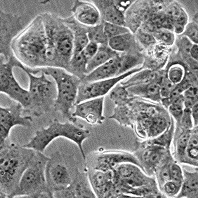

MCF-7

Морфология: эпителиоподобная

Способ культивирования: монослойный